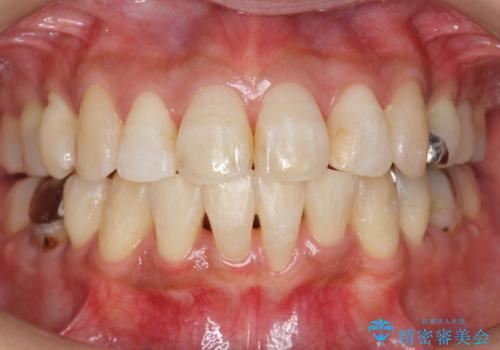

前歯のデコボコを改善 インビザライン矯正

担当医 藤巻太一朗